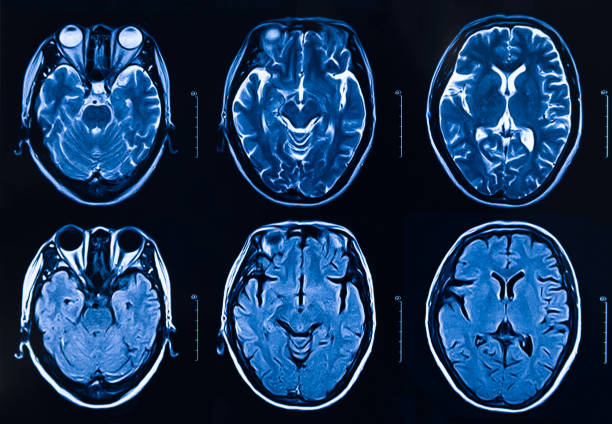

뇌졸중 전조승상 다섯 번째는 두통입니다. 뇌출혈과 마찬가지로 뇌에서 생긴 문제기 때문에 두통은 일반적으로 나타납니다. 하지만 두통은 특별히 증상이 없더라도 나타날 수 있는 증상이기 때문에 무시받는 경우가 많아 오히려 더 무서울 수 있습니다. 따라서 평소와 다른 두통이 느껴진다면 뇌 관련 검사를 빠르게 받는 것이 필요합니다.